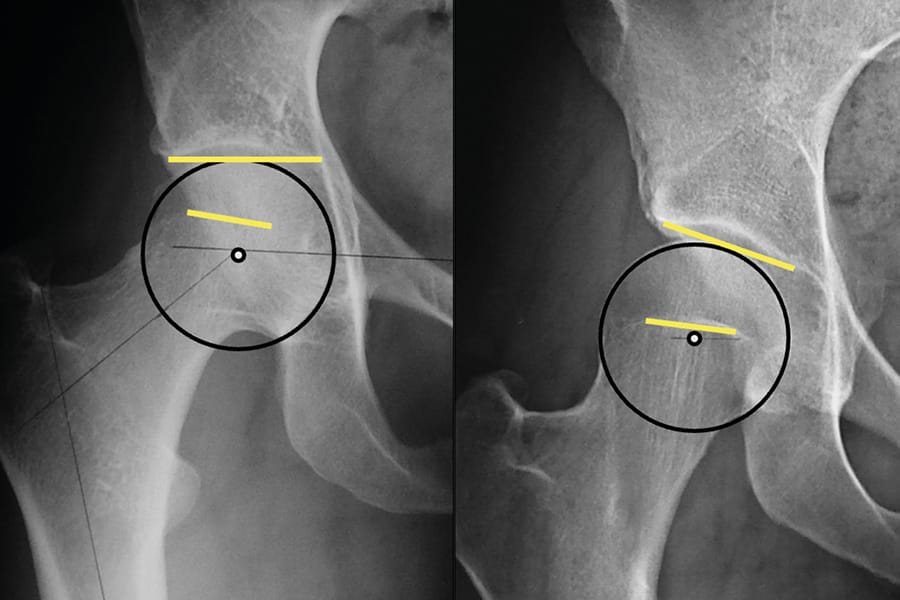

Actualité Variations de l’offset acétabulaire entre planification pré opératoire (mediCAD©) et mesure radiographique post opératoire , Anatole MATRAY Department of Orthopaedic surgery, CHU de Poitiers, Poitiers, France , Clément CAZEMAJO Department of Orthopaedic surgery, CH La Rochelle, La Rochelle, France , Mathieu Severyns Centre Sablais de l’Appareil Locomoteur, Clinique Porte Océane, Les Sables d’Olonne, France 🖂 mathieu.severyns@hotmail.fr N°350 - Janvier 2026 ● 17 min de lecture